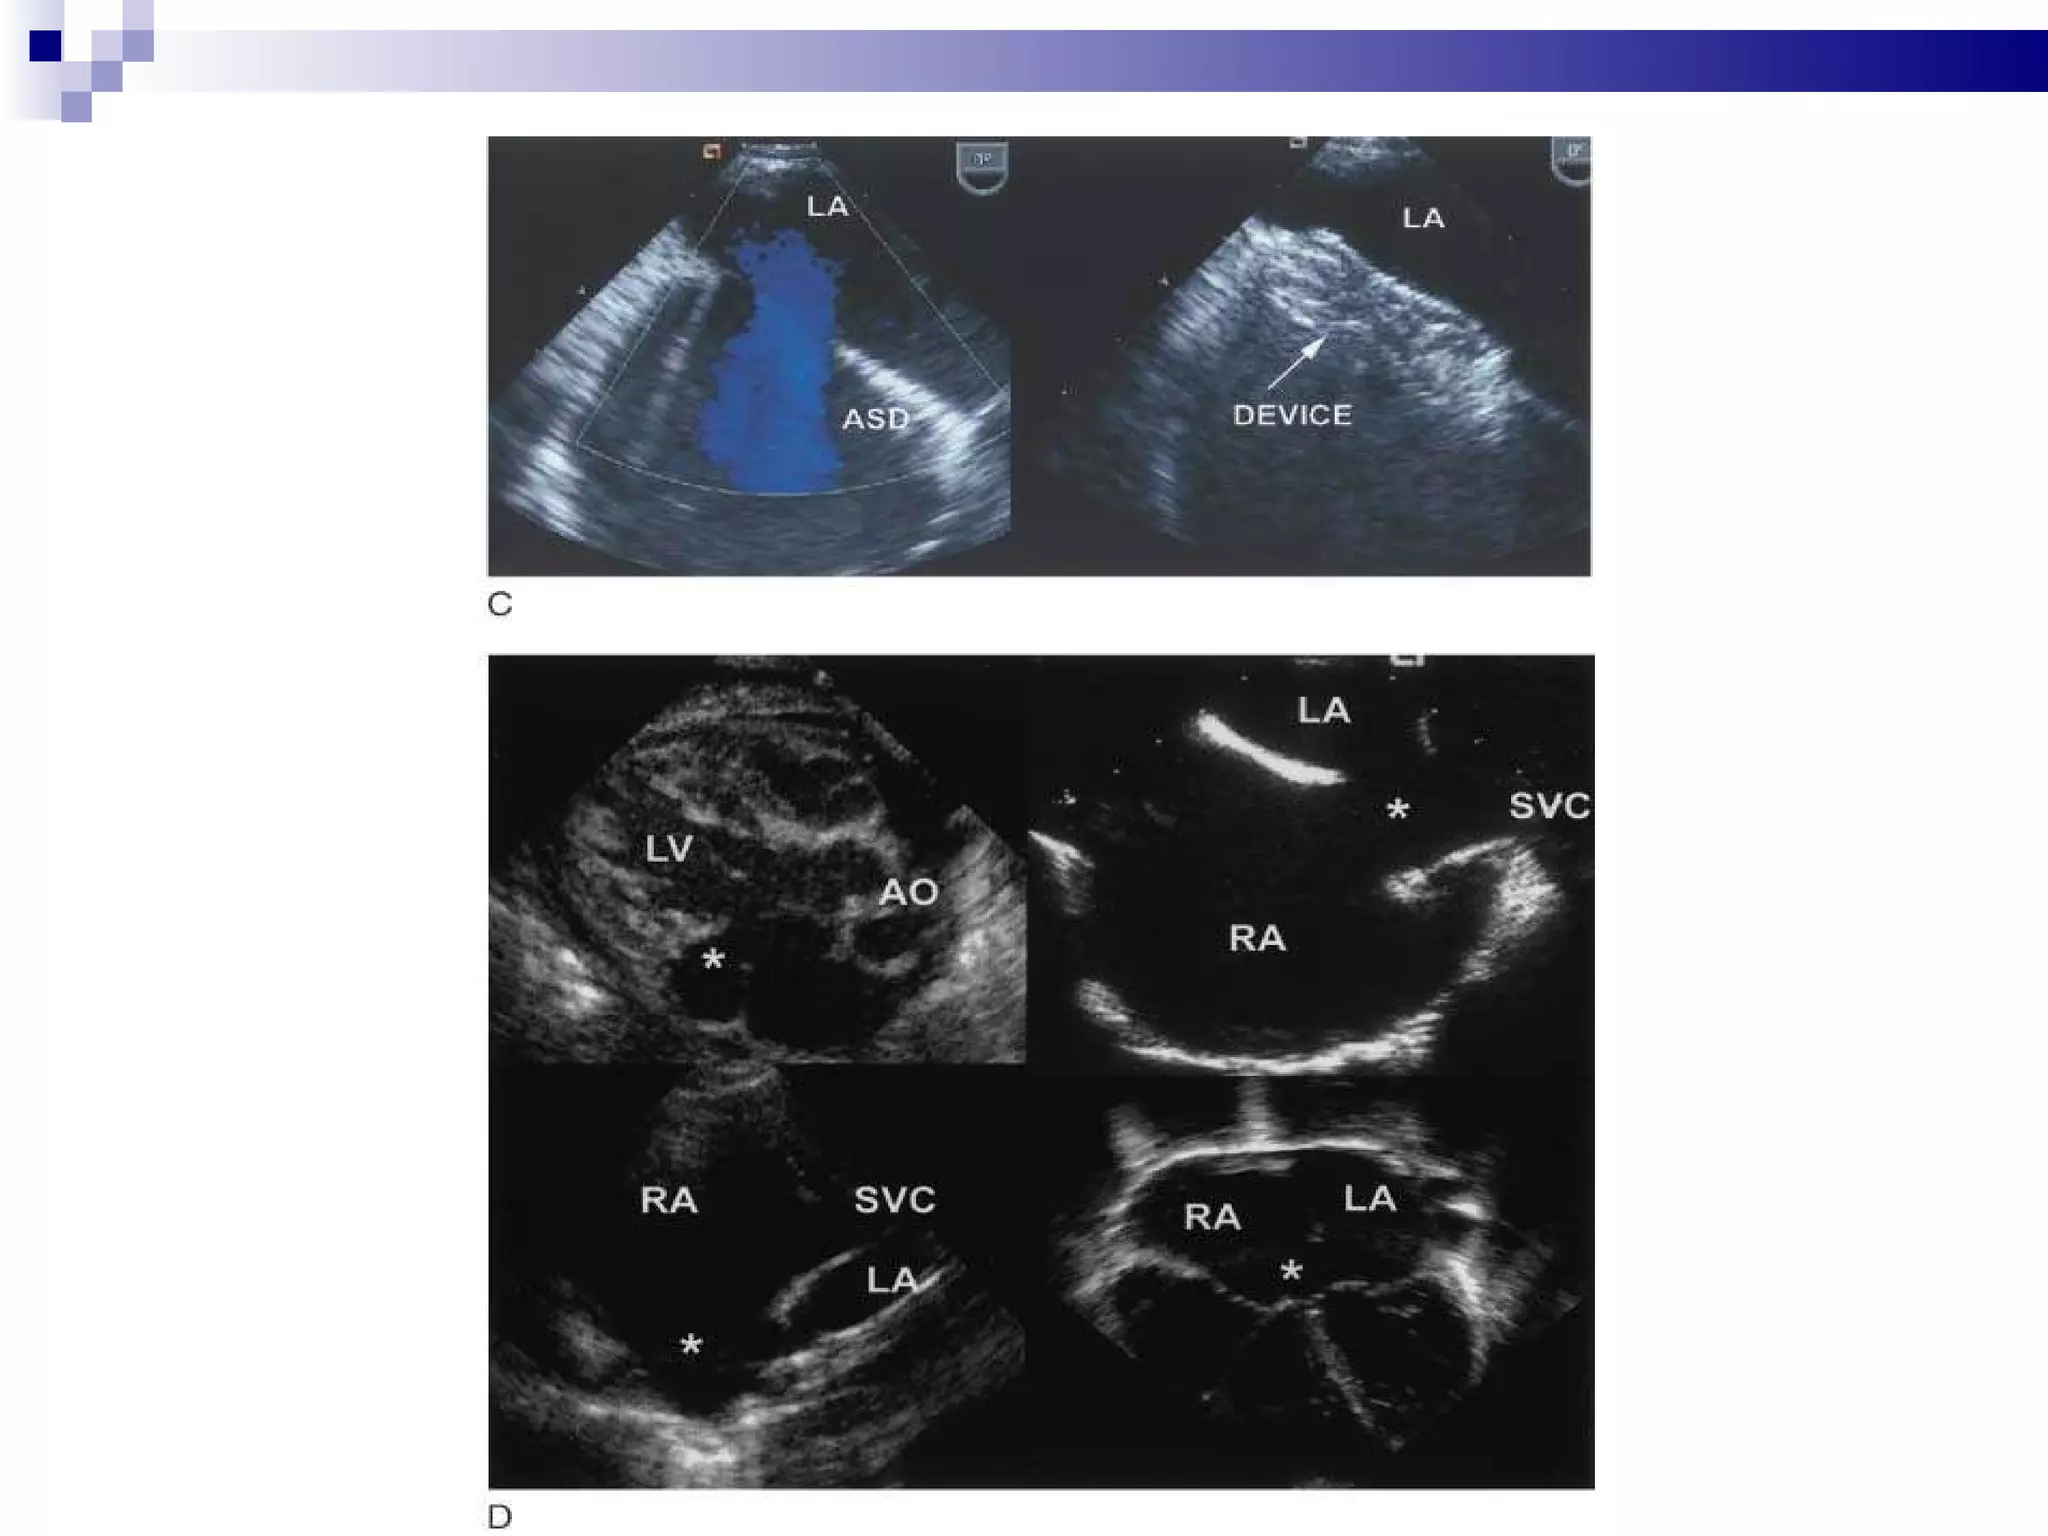

Percutaneous ASD closure Percutaneous closure of an ASD is indicated for the closure of secundum ASDs with a sufficient rim of tissue around the septal defect so that the closure device does not impinge upon the  SVC ,  IVC , or the  tricuspid  or  mitral  valves.  The  Amplatzer  Septal Occluder (ASO) is commonly used to close ASDs. The ASO consists of two self-expandable round discs connected to each other with a 4 mm waist, made up of 0.004–0.005´´ Nitinol wire mesh filled with Dacron fabric. Implantation of the device is relatively easy. The prevalence of residual defect is low.  Percutaneous closure is the method of choice in most centres.

Percutaneous ASD closurePercutaneous closure of an ASD is indicated for the closure of secundum ASDs with a sufficient rim of tissue around the septal defect so that the closure device does not impinge upon the SVC , IVC , or the tricuspid or mitral valves. The Amplatzer Septal Occluder (ASO) is commonly used to close ASDs. The ASO consists of two self-expandable round discs connected to each other with a 4 mm waist, made up of 0.004–0.005´´ Nitinol wire mesh filled with Dacron fabric. Implantation of the device is relatively easy. The prevalence of residual defect is low. Percutaneous closure is the method of choice in most centres.